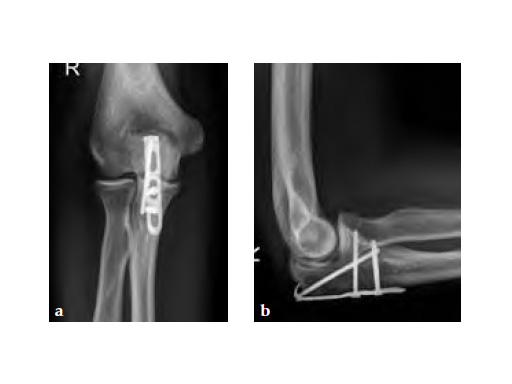

The LCP Hook 3.5 enables tension-band plating with use of 3.5mm screws. The Hook 3.5 was primarily intended for the treatment of simple fractures of the olecranon as well as osteotomies of the olecranon following distal humeral fracture. It has also shown benefits in avulsion fracture of the distal tibia and fibula.

Simple olecranon fractures and osteotomies as well as avulsion fractures of the medial and lateral malleolus treated with traditional tension-band fixation methods are often followed by complications. This is especially evident in patients with poor bone stock and complications include loss of reduction, migration of K-wires and hardware prominence. The LCP Hook 3.5 is a satisfactory alternative fixation.

30-year-old male.

Fig 3ab X-rays 5 months postoperatively.